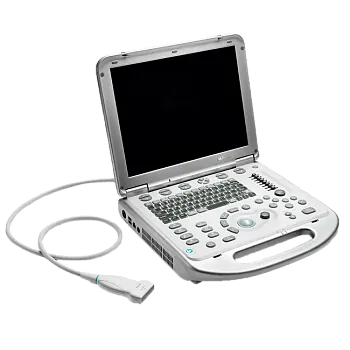

Портативный ультразвуковой аппарат GE Healthcare Logiq e

Особенности системы

УЗИ аппарат LOGIQ e — это высочайшее качество визуализации, настоящая универсальность и компактность. Обновленная версия системы — LOGIQ e R9 — обеспечивает ещё более высокий уровень качества изображений для более широкого спектра комплексных исследований, включая интраоперационные и малоинвазивные вмешательства. Аппарат составит достойную конкуренцию стационарным системам среднего и высокого класса, как в плане возможностей, так и цены.

Систему отличает наличие датчиков со сверхвысокими частотами сканирования, эталонная чувствительность доплеровских режимов для сосудистых исследований, в том числе наиболее сложных транскраниальных, а также высокая частота кадров, которая необходима для качественных кардиологических исследований.

Портативный ультразвуковой сканер Logiq e одинаково эффективно решает диагностические задачи при проведении абдоминальных, сосудистых, кардиологических, акушерско-гинекологических исследований и исследовании поверхностных органов. Позволяет легко работать с разными пациентами от новорожденных до взрослых с «лишним весом».

Аппарат снабжен рядом инструментов и свойств, обуславливающих его специализацию для анестезиологии и реанимации, офтальмологии, флебологии, ревматологии, маммологии, поддержки малоинвазивных вмешательств, спортивной медицины.

Небольшие габариты и малый вес системы позволяют легко использовать её на выезде. С другой стороны Logiq e может быть укомплектован тележкой с тремя активными портами для подключения датчиков, что позволяет полностью воспроизвести функционал полноценной стационарной системы для размещения в кабинете.

Некоторые характеристики консоли

- Масса 5 кг.

- Быстрая загрузка системы (менее 1 минуты).